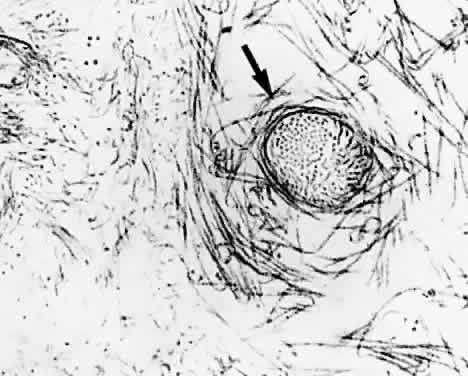

Fig. 16. Vitreoretinal interface in youth. A: Dark-field microscopy of the posterior vitreous in a 14-year-old boy. The sclera, choroid, and retina were dissected off the corpus vitreus, which remains attached to the anterior segment. In contrast to adults, there is an extra layer of tissue that remained adherent to the posterior vitreous cortex when the retina was dissected off. The white arrow indicates the location of the fovea. The circular structure below this location is the prepapillary hole in the posterior vitreous cortex. Emanating from this hole are linear, branching structures (black arrows) that correspond to the location of the retinal vessels. B: Scanning electron microscopy of the tissue described in (A) demonstrates many round structures adherent to the posterior aspect of the tissue. Bar = 10 μm. C: Higher magnification showing the attachment of one of these round structures. There appears to be an indentation or hole on the posterior aspect of this structure. Bar = 1 μm. D: Transmission electron microscopy of this specimen identifies this tissue as the internal limiting lamina (ILL) of the retina attached to the posterior vitreous cortex. The round structures are identified as the inner portion of Müller cells that remained adherent to the posterior aspect of the ILL, with a hole on the posterior aspect of the inner portion of the Müller cell where it was torn away from the rest of the cell body (×20,800). (From Sebag J. Age-related differences in the human vitreoretinal interface. Arch Ophthalmol 109:966, 1991, with permission)

There are cells embedded within the posterior vitreous cortex (Fig. 18) known as hyalocytes. Situated 20 to 50 μm from the ILL of the retina, these mononuclear cells are widely spread apart in a single layer (Fig. 19). The highest density of hyalocytes is in the region of the vitreous base, followed by the posterior pole, with the lowest density at the equator. Derived from circulating monocytes and renewed every 6 months, hyalocytes are oval or spindle-shaped and are 10 to 15 μm in diameter. They contain a lobulated nucleus, a well-developed Golgi complex, smooth and rough endoplasmic reticula, many large periodic acid-Schiff-positive lysosomal granules, and phagosomes (Fig. 20). Balazs72 noted that hyalocytes are located in the region of highest HA concentration and suggested that these cells may be responsible for vitreous HA synthesis, which may also be true of vitreous collagen.

Fig. 19. Human hyalocytes in situ. Phase-contrast microscopy of flat-mount preparation of posterior vitreous cortex from the eye of an 11-year-old girl obtained at autopsy (courtesy of New England Eye Bank, Boston, MA). No stains or dyes were used in this preparation. Mononuclear cells are distributed in a single layer within the vitreous cortex (7times;115).

Fig. 20. Ultrastructure of human hyalocyte. A mononuclear cell is seen embedded within the dense collagen fibril (black C) network of the vitreous cortex. There is a lobulated nucleus (N) with a dense marginal chromatin (white C). In the cytoplasm, there are mithochondria (M), dense granules (arrows), vacuoles (V), and microvilli (Mi). (×11,670.) (Courtesy of Joe Craft and Dan Albert, MD)